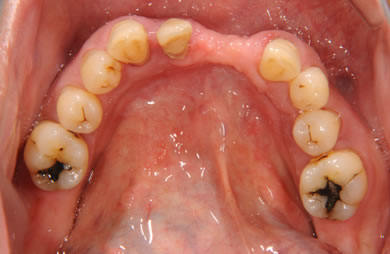

骨再生スピードインプラント治療+AGC連結セラミック治療+セラミック治療

| 治療方針 | ソケットリフト法により上顎洞底部を拳上することにより、骨の無い部分に骨をつくってあげ、インプラント治療を可能にする。さらに歯周病により組織の破壊が著しいので、AGC連結セラミック治療により上顎の審美的回復を行う。 | ||||||||||||||||||||||||||||||||

| 治療内容 | インプラント7本(抜歯AGC即日スピードインプラント+ソケットリフト)、AGCハイブリッドセラミック連結ブリッジ1装置(上顎)ハイブリッドセラミック8本 | ||||||||||||||||||||||||||||||||